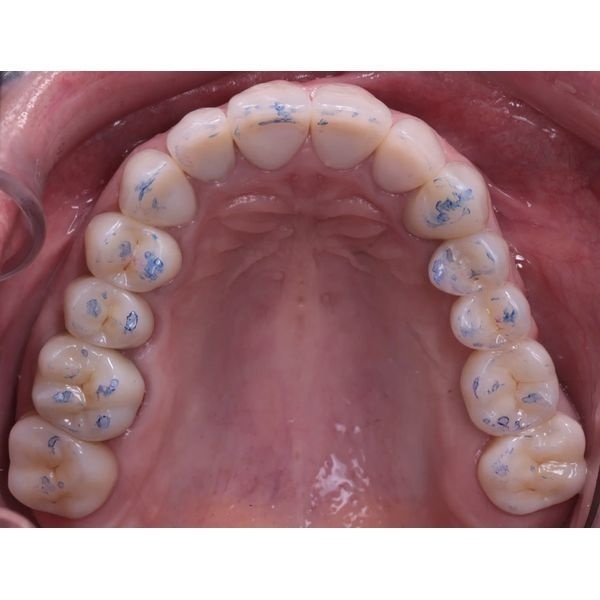

При моделировании будущих зубов использовались данные аксиографии: угол суставного пути (наклон ската суставной ямки), переднюю направляющую (угол наклона центральных зубов), угол окклюзионной плоскости по сфере Монсона (высота боковых зубов). После провели примерку будущих конструкций в полости рта. Когда всё согласовали (женщина скорректировала эстетические параметры — размер и форму), конструкции зафиксировали на пару месяцев и сделали контрольное МРТ. Она показала расширение суставной щели и более корректное положение суставной головки слева.

В этом случае нам удалось добиться оптимального окклюзионного контакта. На динамических и статических пробах видно плотное, равномерное смыкание всех зубов. Это не только эстетически выигрышно, но и функционально: теперь жевание стало эффективнее, а нагрузка на суставы — физиологичнее.